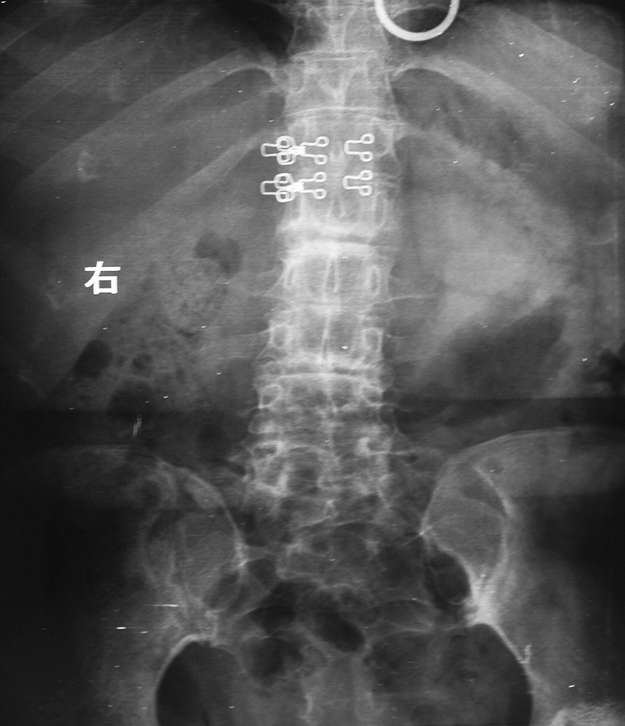

女性34岁,左髋疼痛5年,伴有背部疼痛,腰部活动受限,局部有压痛。

腰椎、左侧骶髂关节及双侧髋关节间隙变窄,左侧明显且有软骨下局部骨硬化,首先考虑强制性脊柱炎,鉴别包括类风湿性关节炎、沙门氏菌骨关节感染及布氏菌骨关节感染等。

腰椎、左侧骶髂关节及双侧髋关节间隙变窄,左侧明显且有软骨下局部骨硬化,首先考虑强制性脊柱炎.

腰椎竹节样改变,考虑强直性脊柱炎